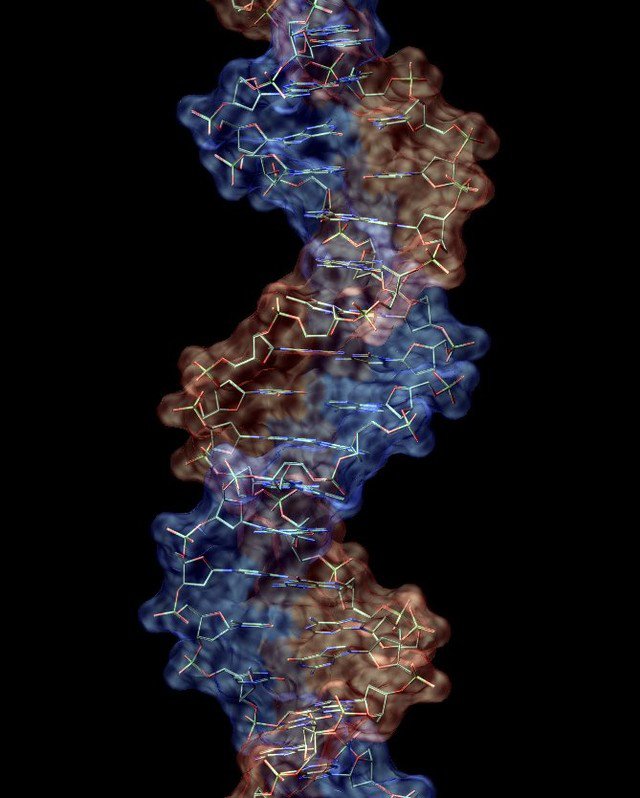

2. Phát triển những loại thuốc mới hiệu quả hơn

Để đưa một phương thuốc đi vào cuộc sống hiện đại thì phải trải qua hàng nghìn cuộc thử nghiệm, hàng chục năm phát triển và thậm chí tiêu tốn hàng triệu USD. Đấy là còn chưa tính đến những trường hợp thất bại trước khi được đưa vào sản xuất.

Nhưng mọi chuyện sẽ chỉ là quá khứ với sức mạnh của máy tính lượng tử khi mà những cỗ máy này có thể đưa ra hàng nghìn kiểu kết hợp phân tử có thể xảy ra của loại thuốc đang nghiên cứu, từ đó những nhà khoa học có thể nhanh chóng tìm ra phương án tối ưu nhất àm không phải tốn thời gian như trước.

Ngoài ra, máy tính lượng tử cũng có thể đủ khả năng để giải mã bộ gien của con người, đây là cơ sở tạo nên bước đột phá của ngành y học trong tương lai.